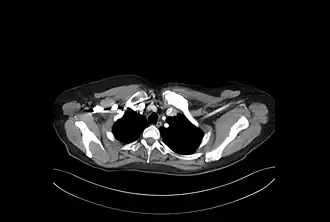

En las radiografías y otras técnicas de imagen (TAC o RMN) puede observarse crecimiento –hiperostosis- y esclerosis de los extremos mediales de las clavículas. Igualmente, pueden observarse áreas osteolíticas y áreas esclerosas. Similar afectación se puede observar en el esternón, en especial en el manubrio y en los segmentos anteriores de las costillas. Fuera de la pared torácica se han descrito hallazgos similares en los cuerpos vertebrales –con imágenes de espondilodiscitis, osteoesclerosis y osificaciones paravertebrales-, en la mandíbula, en huesos largos –sobre todo metáfisis de fémur distal y tibia proximal- y afectación de sacroilíacas. En los huesos largos la imagen es semejante a la osteomielitis crónica, pero sin abscesos, ni secuestros óseos.[11]

Aporta gran información la gammagrafía ósea, siendo es muy típico el patrón de hipercaptación esternoclavicular simétrica en "cabeza de toro", donde el manubrio esternal representa el cráneo y las articulaciones esternoclaviculares y las clavículas corresponden a los cuernos.[15]